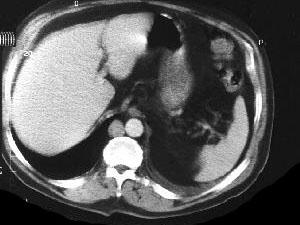

问题 中年男性,间断性腰背痛4个月,突发左下肢全肢水肿,小腿有张力性水泡,水肿累积会阴部,常规胸腹部CT扫描如图所示,你认为哪些征像及结论正确 ( )

选项 A、奇静脉变细 B、正常CT表现 C、下腔静脉变细 D、奇静脉增粗 E、下腔静脉缺如

答案 DE